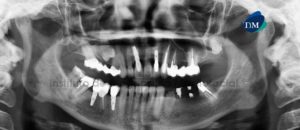

Paciente femenino de 64 años de edad, es referido al Instituto de Diagnóstico Maxilofacial para evaluación tomográfica de implantes dentales. A la evaluación de la